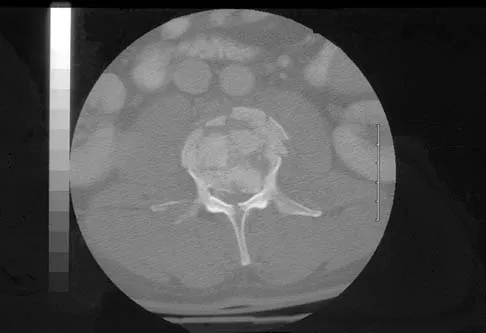

Question 49High Yield

A 46-year-old man has incomplete paraplegia after being involved in a motor vehicle accident. The CT scan shown in Figure 5 reveals marked canal compromise. What is the most appropriate management to improve neurologic status?

Explanation

According to a study by the Scoliosis Research Society, the use of anterior decompression is most predictable for improving neurologic status. This is particularly true of bowel and bladder functional loss. Laminectomy is contraindicated because it further destabilizes the spine. Posterior instrumentation and indirect reduction through distraction and ligamentotaxis only incompletely decompress the compromised canal and are successful only if performed within 48 hours of injury. While some improvement may occur with closed management, the amount of recovery is less than that achieved with surgical decompression. A posterior approach and instrumentation may be added to the anterior decompression based on the characteristics of associated injuries to the posterior element. Gertzbein SD: Scoliosis Research Society multicenter spine fracture study. Spine 1992;17:528-540. Garfin SR, Vaccaro AR (eds): Orthopaedic Knowledge Update: Spine. Rosemont, IL, American Academy of Orthopaedic Surgeons, 1997, pp 197-215.